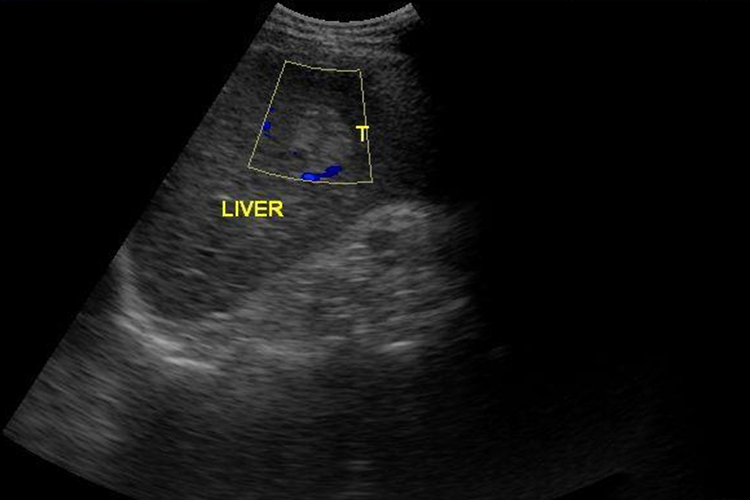

- 如果肝上血管瘤直径在5cm以下,并且患者没有任何症状,如腹部疼痛、消化不良等。通常建议定期进行超声或其他影像学检查,以监测血管瘤的大小、形态等变化,无需进行手术治疗。

- 有些肝上血管瘤虽然直径不足5cm,但生长的位置相对较为安全,远离重要的血管、胆管等结构,即使血管瘤较小,其对周围组织的影响也较小,手术的必要性相对较低,可先采取观察和随访策略。